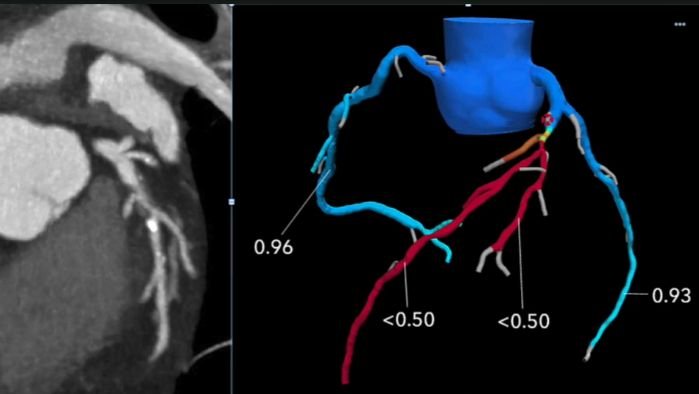

Offering enhanced diagnostic precision compared to standard stress tests, abnormal perfusion scans strongly indicate coronary artery disease (CAD). MPI plays a crucial role in determining whether patients should undergo angiograms, angioplasty, bypass surgery, or medical management. It’s also instrumental in monitoring the effectiveness of these treatment approaches.MPI and coronary angiography (conventional or CT) provide complementary yet distinct information for diagnosing and evaluating CAD. While coronary angiography detects atherosclerosis, MPI assesses ischemia’s hemodynamic significance, guiding further therapeutic strategies. Notably, patients with angiographically confirmed CAD but negative MPI results exhibit similarly low event rates.